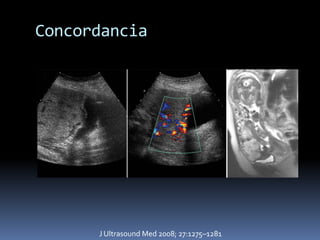

Concordancia

J Ultrasound Med 2008; 27:1275–1281

Concordancia J Ultrasound Med 2008; 27:1275–1281